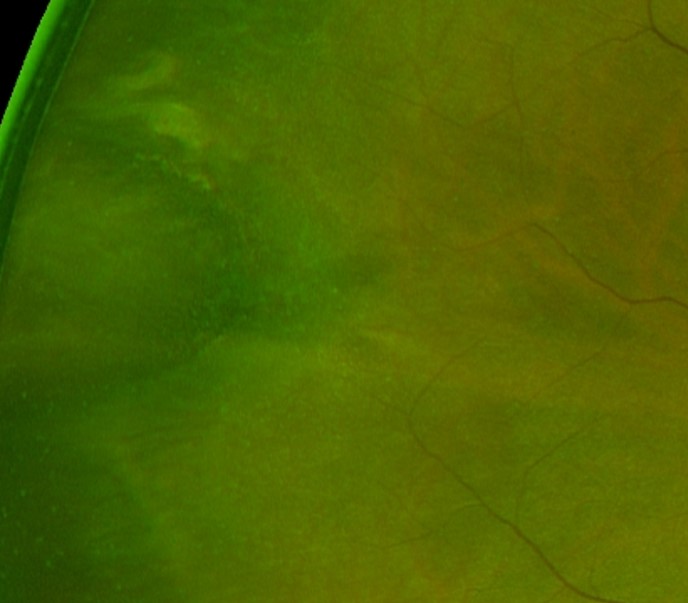

An oral bay is formed by the joining of two or more dentate processes at the ora serrata. These dentate processes may join (completely enclosed) or have a gap remaining (partially enclosed oral bay).

Oral bays may be confused with a retinal hole on examination however oral bays do not increase the risk of retinal detachment.

Oral pearls are drusen-like deposits located between the RPE and Bruch’s membrane. The deposits are white and glistening on examination and may be found within an oral bay or adjacent to the dentate processes.